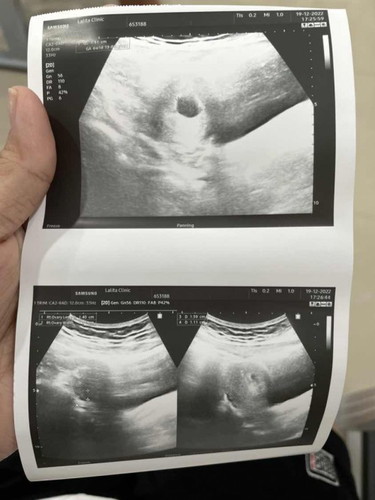

ท้องได้5week ค่ะอยากทราบว่าจะได้ยินเสียงหัวใจและเห็นเจ้าตัวเล็กตอนกี่weekค่ะ

แม่บ้านนี้ท้องได้ 5 w+1 dค่ะ อยากทราบว่า5wแม่ๆบ้านอื่นเห็นตัวเล็กรึยังคะ